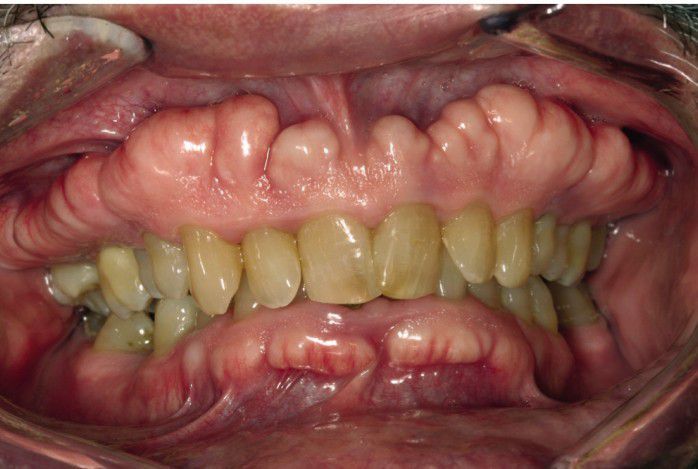

Exostosis

Multiple buccal exostoses of the maxillary and mandibular alveolar ridges.